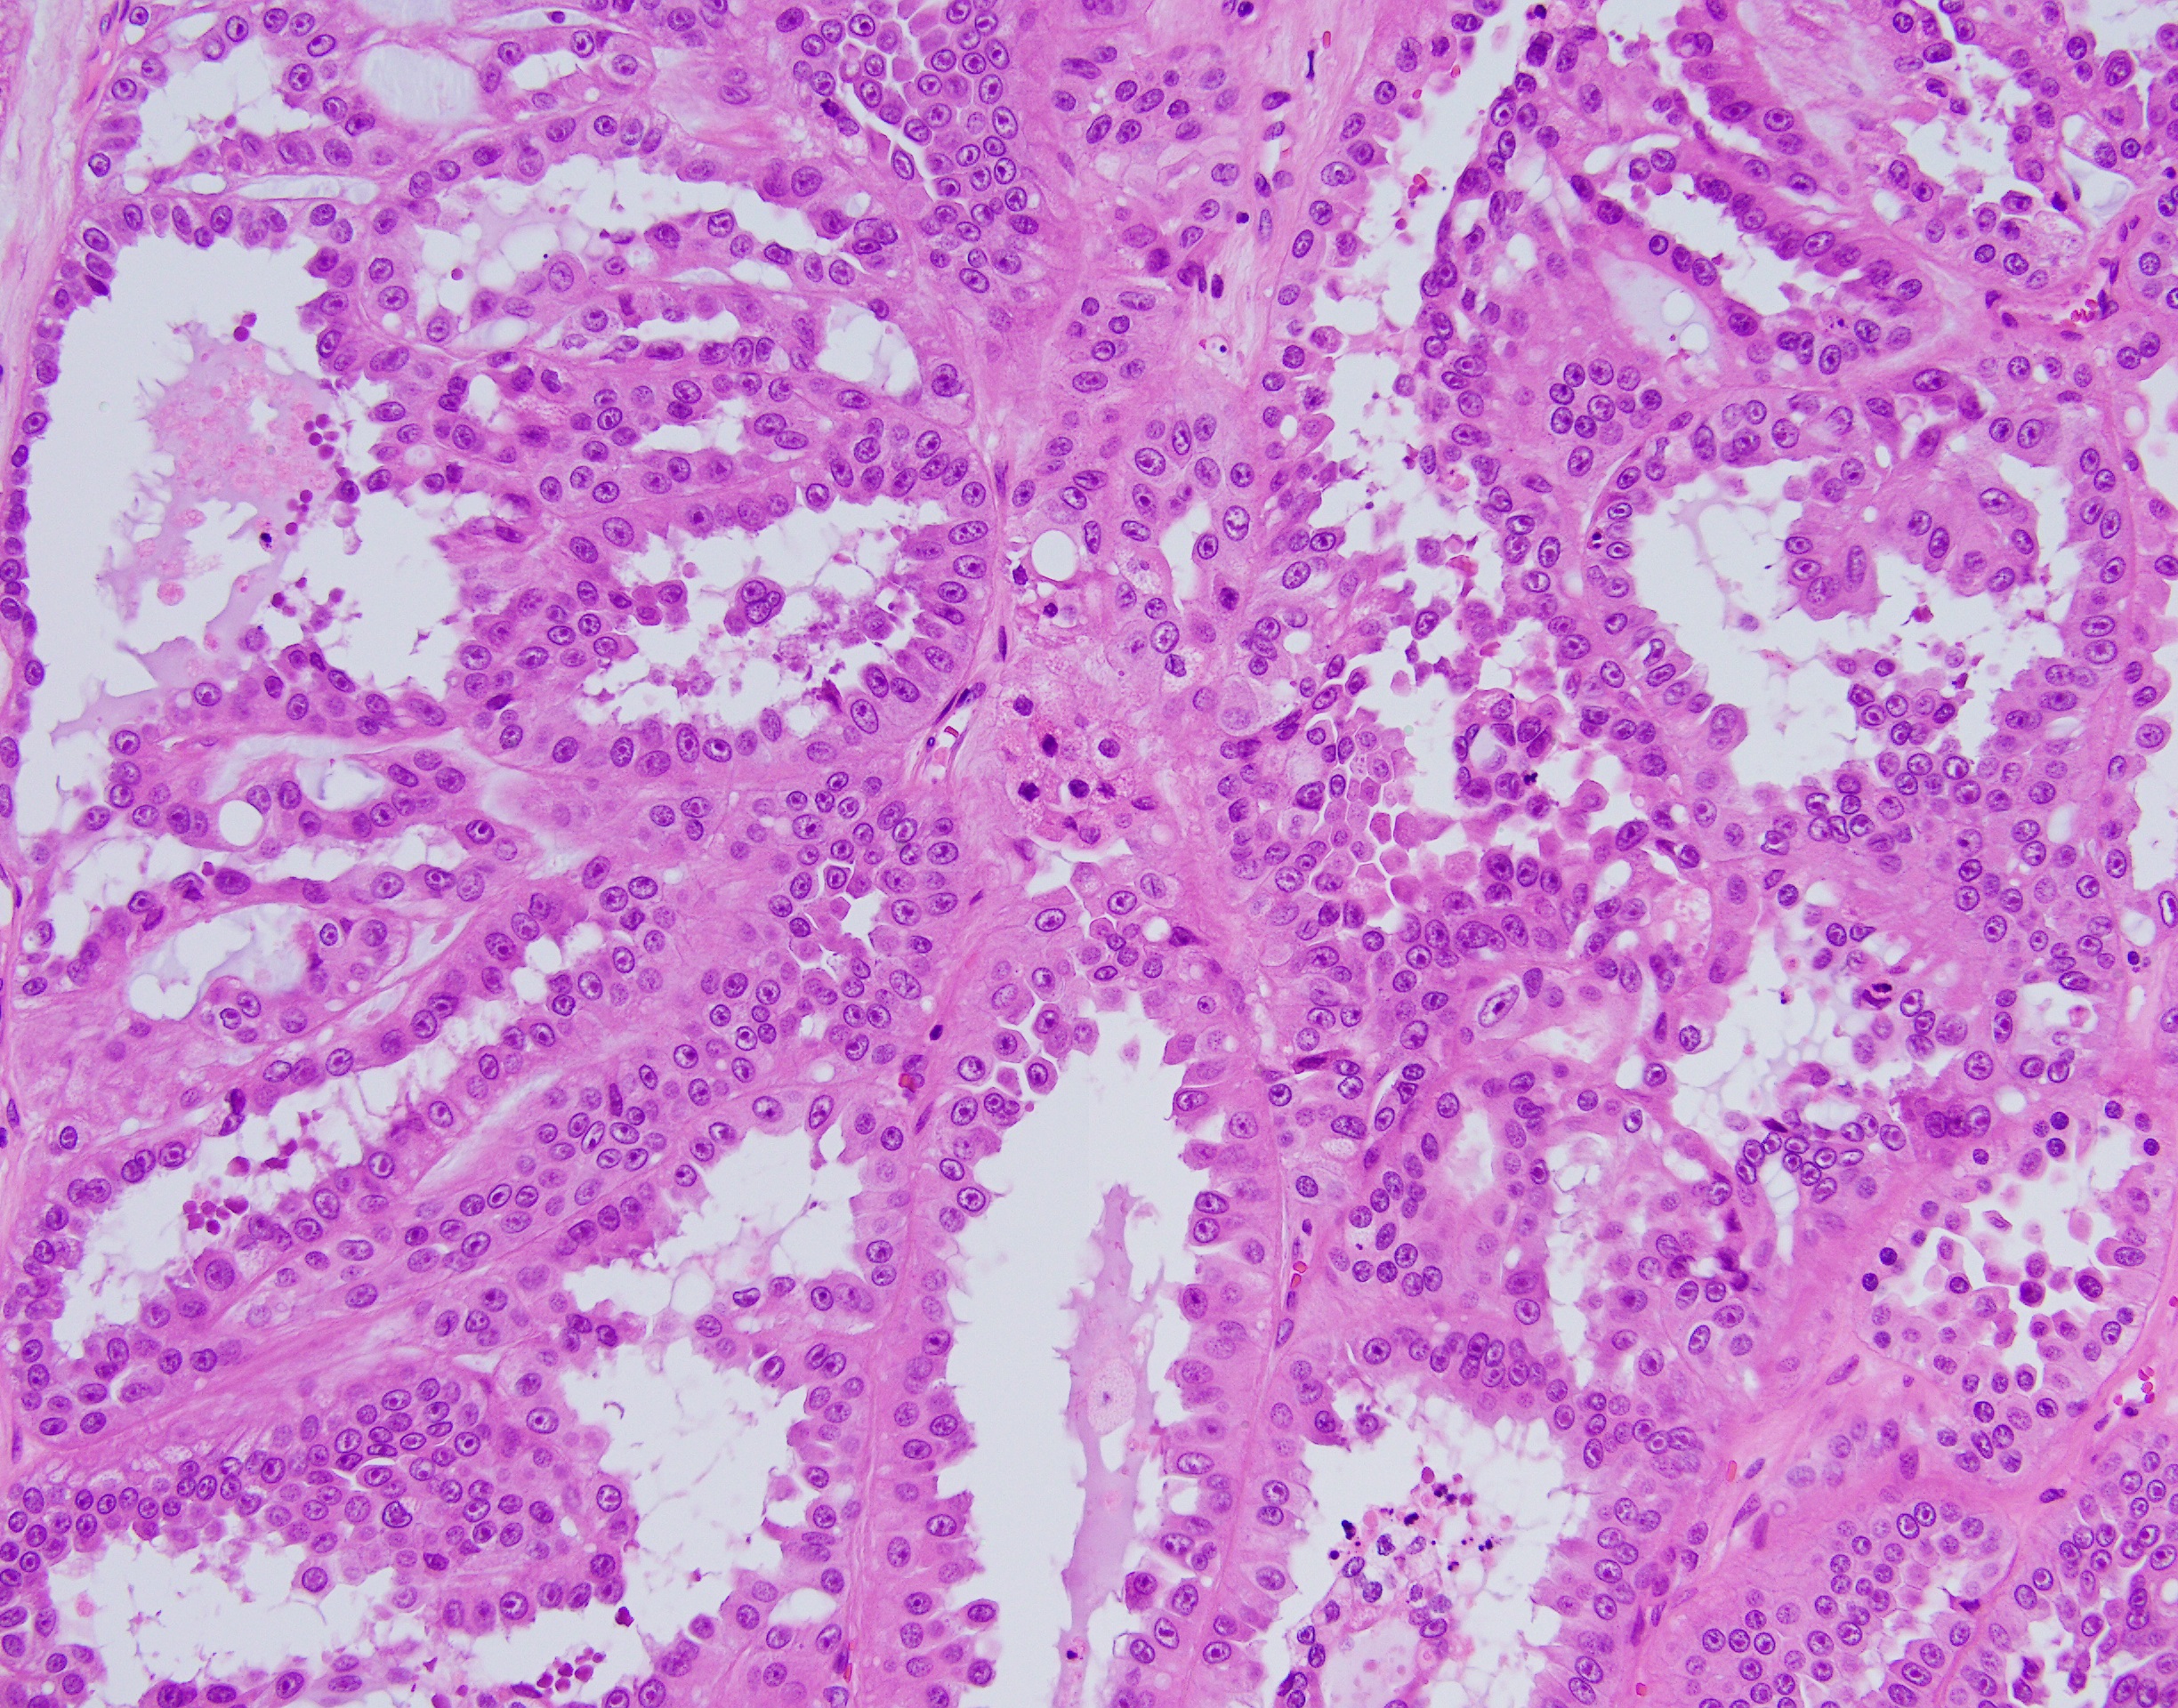

35 year-old-male with an 8 cm well-circumscribed, solid mass located in the upper pole of the left kidney with associated para-aortic metastasis. H&E, and IHC stains are shown.

Histologically, FH-deficient RCCs were originally described as type 2 papillary RCC and occasionally as collecting duct carcinoma (CDC), with a spectrum of architectural patterns including papillary, tubulopapillary, tubular, cribriform, solid and cystic elements. The morphological hallmarks of HLRCC are characteristic nuclear features: a large nucleus with a very prominent inclusion-like eosinophilic nucleolus surrounded by a perinucleolar halo. Based on these architectural and nuclear features, the differential diagnosis of HLRCC could include a variety of high-grade RCCs of different histological subtypes, particularly type 2 papillary RCC, CDC, or high-grade RCC, unclassified. Recently, an expanded histological spectrum of FH-deficient RCC has been described, including tubulocystic carcinoma with poorly differentiated foci, and SDH-deficient RCC like morphology was observed in FH-deficient RCC.